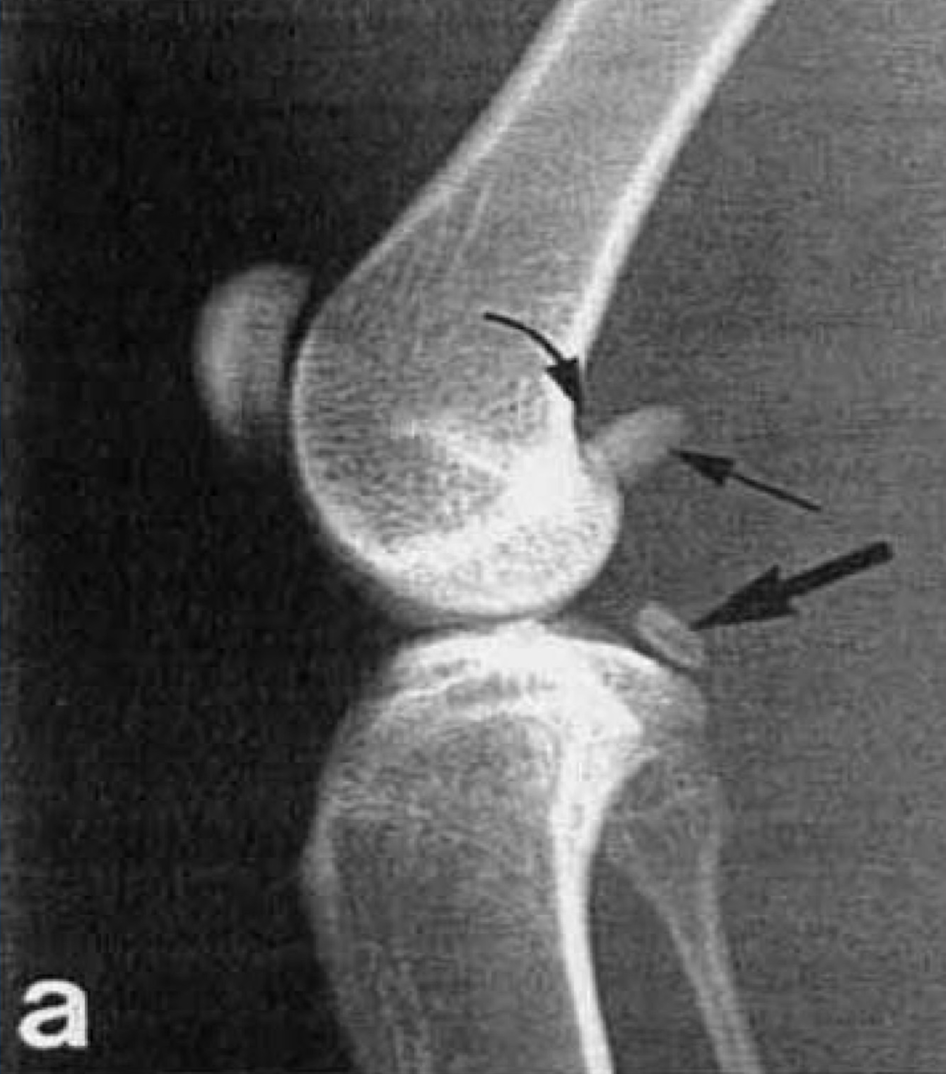

1

lateral collateral ligament

2

medial collateral ligament

3

lateral meniscus

Fibrocartilage

4

medial meniscus

6

anterior cruciate ligament

7

articular cartilage

hyaline cartilage

8

femur

9

tibia